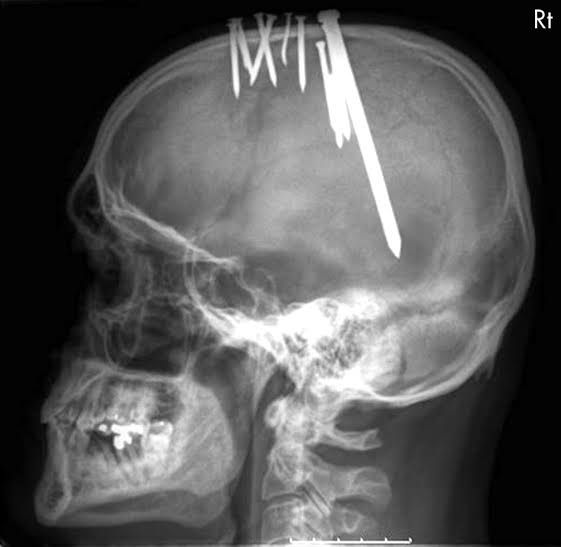

44-year-old man came to the emergency department wearing a baseball cap and complaining of severe headaches that had progressively worsened over the preceding 11 weeks. when the patient removed his cap to it was revealed that an assortment of metallic objects are embedded in his scalp. Plain radiographs showed 11 nails penetrating into his brain.Β His detailed history presented a diagnosis of paranoid schizophrenia, and the patient confirmed that he had hammered a nail into his head each week for the past 11 weeks in order to rid him of evil. The nails were removed with the patient under general anesthesia, and he made an uncomplicated recovery with no neurological deficits Image by : https://images.app.goo.gl/ThCkwbdthDJcEKJ29 Full article at: https://mindhacks.com/2007/12/17/man-hammers-nail-into-head-every-week-for-11-weeks/

The nails were penetrating all the way to the brain and yet he recovered from the injury and was sent to the psychiatry for follow up.